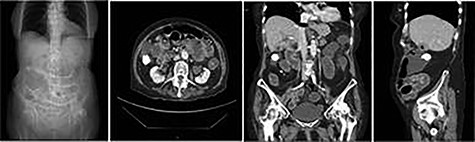

Plain abdominal X-ray demonstrated a calcified lesion on the right as well as distended loops of small bowel (Fig. 1). Abdomino-pelvic contrast CT scan showed an abnormal gallbladder containing pockets of air and a fistulation through the lateral part of D2,with a 22 mm calcified lesion within the ascending colon (Fig. 2a–d). Based on the history, physical examination and CT scan findings, our diagnosis was of resolving gallstone ileus.

Plain abdominal X-ray at presentation demonstrating gallstone as well as distended loops of small bowel.

a,b,c,d: CT images scout, axial, coronal and sagittal planes, respectively demonstrating gallstone as well as distended loops of small bowel.